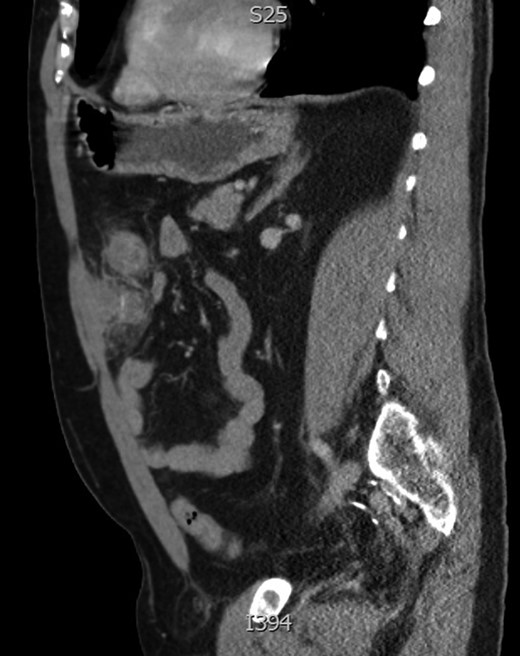

Sagittal image of anterior abdominal collection with central enhancement representing foreign body.

A 61-year-old gentleman presented to the emergency department with 4 day history of worsening left sided abdominal pain, localized to the left upper and predominantly left lower quadrant. This was associated with nausea and subjective fevers. He had no changes to his bowel habits and had no vomiting or urinary symptoms. Physical examination revealed a septic picture with a body temperature of 38.4, HR of 110. He was tender in the Left lower quadrant with localized guarding. Laboratory results showed a white cell count of 10.4 × 109 with neutrophils of 7.90 × 109 and a CRP of 127. A CT of the abdomen showed inflammatory changes present involving the transverse colon located left of the midline, this was associated with a low density peripherally enhancing abscess measuring 2.5 × 3 × 2.4 cm (Figs 1 and 2).